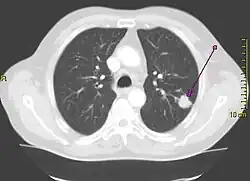

| Reconstrução em 3D de uma tomografia computadorizada de tórax mostrando um tumor no pulmão esquerdo (marcado por uma seta) | |

Os sintomas mais comuns são tosse (também a hemoptise), perda de peso e dificuldades na respiração.[7] O câncer de pulmão pode ser visto na radiografia do tórax e na tomografia computadorizada (TC). O diagnóstico é confirmado por uma biópsia, que geralmente é realizada através de uma broncoscopia ou de uma biópsia guiada por TC. O tratamento e o prognóstico dependem do tipo histológico do tumor, do estágio (grau de extensão da doença) e do bem-estar geral do paciente, medido pelo estado funcional. Os tratamentos mais comuns são a cirurgia, a quimioterapia e a radioterapia. O CNPC pode ser tratado com cirurgia, ao passo que o CPC, normalmente, responde melhor à quimioterapia e à radioterapia. Isso se dá, parcialmente, porque o CPC frequentemente se espalha muito cedo e esses tratamentos são melhores em atingir as células que já se deslocaram para outras partes do corpo.[8]

A radiografia de tórax é um dos primeiros métodos investigativos quando um paciente relata sintomas que sugerem um câncer de pulmão. Ela pode revelar uma massa óbvia, alargamento do mediastino (sugestivo de acometimento de linfonodos locais), atelectasia (colapso do alvéolo), consolidação (pneumonia) e derrame pleural.[1] A tomografia computadorizada (TC) é tipicamente utilizada para fornecer mais informações sobre o tipo e a extensão da doença. A broncoscopia ou a biópsia guiada por TC são frequentemente usadas para coletar amostras do tumor para análise histopatológica.[9]